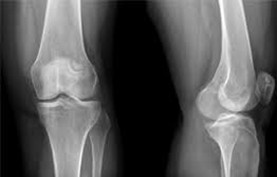

• рентгенография

Рентгенография является основным методом диагностики гонартроза и позволяет определить:

• сужение суставной щели

• наличие остеофитов

• степень деформации сустава